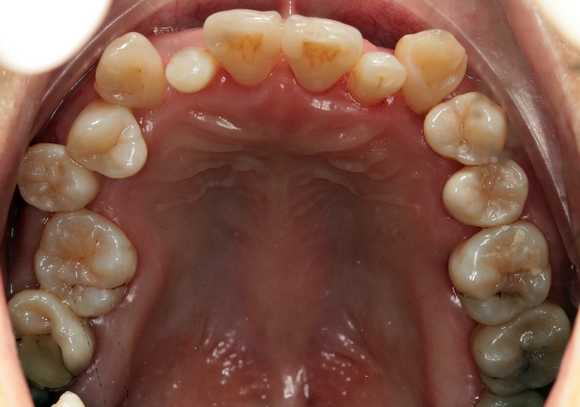

2.牙结石

牙结石是指长期沉积在牙齿上矿化的菌斑,牙结石对牙周组织的危害,主要是构成了菌斑附着同时也是细菌滋生提供了良好生存环境,长期牙结石不清理会产生严重的牙周炎。